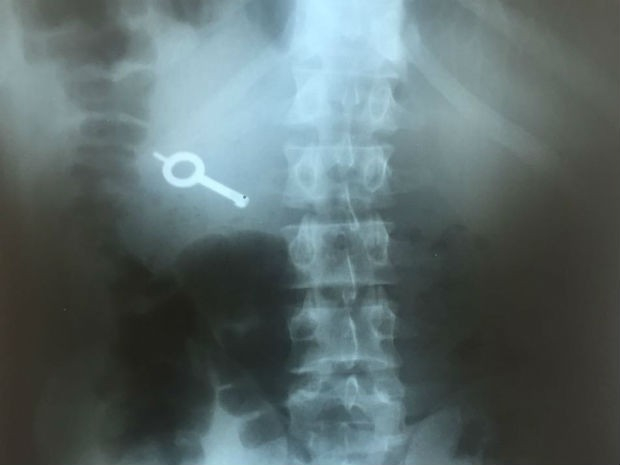

Um deles foi o que engoliu a chave. Ela foi identificada no detector de metais do Hildebrando de Souza. O detento, então, foi encaminhado ao Hospital Municipal, onde fez um raio-X que confirmou a ingestão da chave.

Ele deve permanecer internado no local até expelir o objeto. Segundo a polícia, o preso não estava algemado dentro da cela. A suspeita é a de que ele engolido a chave para usar em uma próxima tentativa de fuga ou para repassar para outro detento.